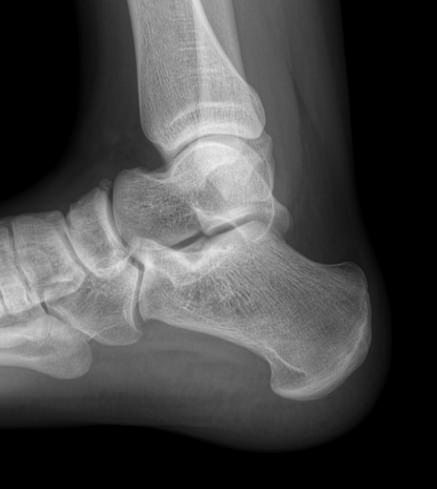

Назад Рентген пяточных костей в боковой проекции

Пяточная кость ― самая крупная среди костей стопы. Нагрузка, приходящаяся на нее, колоссальна. Отсюда и частая травматизация, связанная как со спортом, так и с бытовой и профессиональной деятельностью. Также все патологии, которые развиваются в костной ткани, могут появиться и в пяточной кости. Рентген ― наиболее часто назначаемый вид диагностики при поражении пятки.

На рентгенограмме будут отчетливо видны все структурные изменения, произошедшие с самой пяточной костью и тканями вокруг нее.

Что покажет рентген пяточных костей в боковой проекции

• Целостность кости: переломы, отломки, смещение;

• Состояние костной ткани: разрежение, склерозирование, некроз и другие изменения;

• Конгруэнтность суставных поверхностей и состояние щелей, попавших в область снимка: нормальные, измененные;

• Отечность и инородные тела в мягких тканях пятки;

• Новообразования: опухоли, остеофиты.

Стоит отметить, что остеофиты не являются причиной плантарного фасциита, а вырастают в ответ на хроническое раздражение мягких тканей и свидетельствуют о глубокой стадии заболевания.